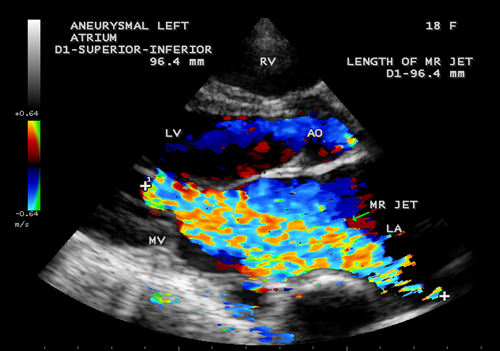

Case 3. Aneurysmal left atrium in a 18 –year old girl due to isolated severe rheumatic mitral regurgitation as shown in Figures 9 to 14. The patient was presented with stroke and treated with anticoagulants and antiplatelet agents and, advised lifelong penicillin prophylaxis and MVR (mitral valve replacement).

Figure 12. Parasternal long axis view showing the severe mitral regurgitation touching the entire length of dilated left atrium and the length of jet is correlating with superior-inferior dimension of the left atrium in an 18-year-old girl

The extreme dilatation of the left atrium is probably related to the jet of regurgitation (or insufficiency), a finding common to all as shown in Figure 12, the jet occupies the entire left atrium as in Figure 13 and a holosystolic pattern in color M-mode echocardiography as shown in Figure 14.